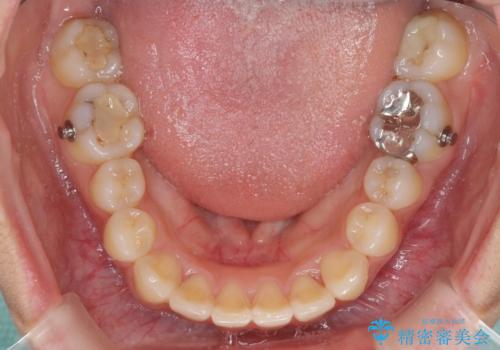

前歯の突出感とデコボコ インビザラインで改善

- 上下前歯のデコボコを気にして来院された患者様です。

インビザラインによる上下歯列の側方拡大と後方移動、IPR(歯と歯の間を削る)にるスペースの獲得により歯列を整えることとしました。

右上の小臼歯は歯根癒着をしており、様々な方法を試みるも動かすことができませんでした。

それでも奥歯のかみ合わせに不自由はなく、歯列をきれいに整えることができました。